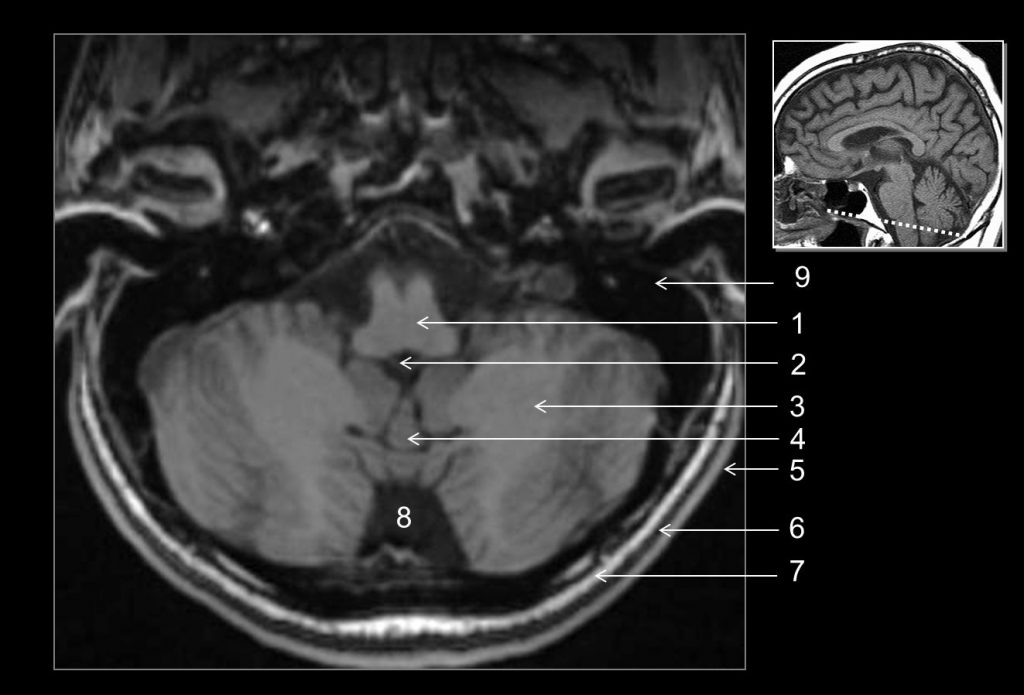

Fig. 48.3 Coupe axiale (IRM) en pondération T1.

1. Moelle allongée. 2. Quatrième ventricule. 3. Hémisphère cérébelleux. 4. Vermis. 5. Scalp. 6. Os occipital (table externe). 7. Os occipital (diploé). 8. Citerne cérébello-médullaire. 9. Rocher.